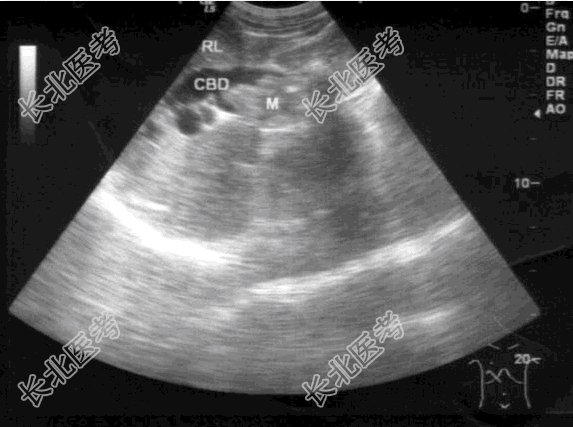

- 单项选择题女,47岁, 皮肤、巩膜黄染,进行性加重2个月余, 腹痛、腹胀,既往有胆结石病史。B超检查如图所示, 根据超声声像图,诊断为

A、胆总管癌

B、胆总管蛔虫

C、胆总管胆泥淤积

D、胆总管结石

E、胆总管癌并结石